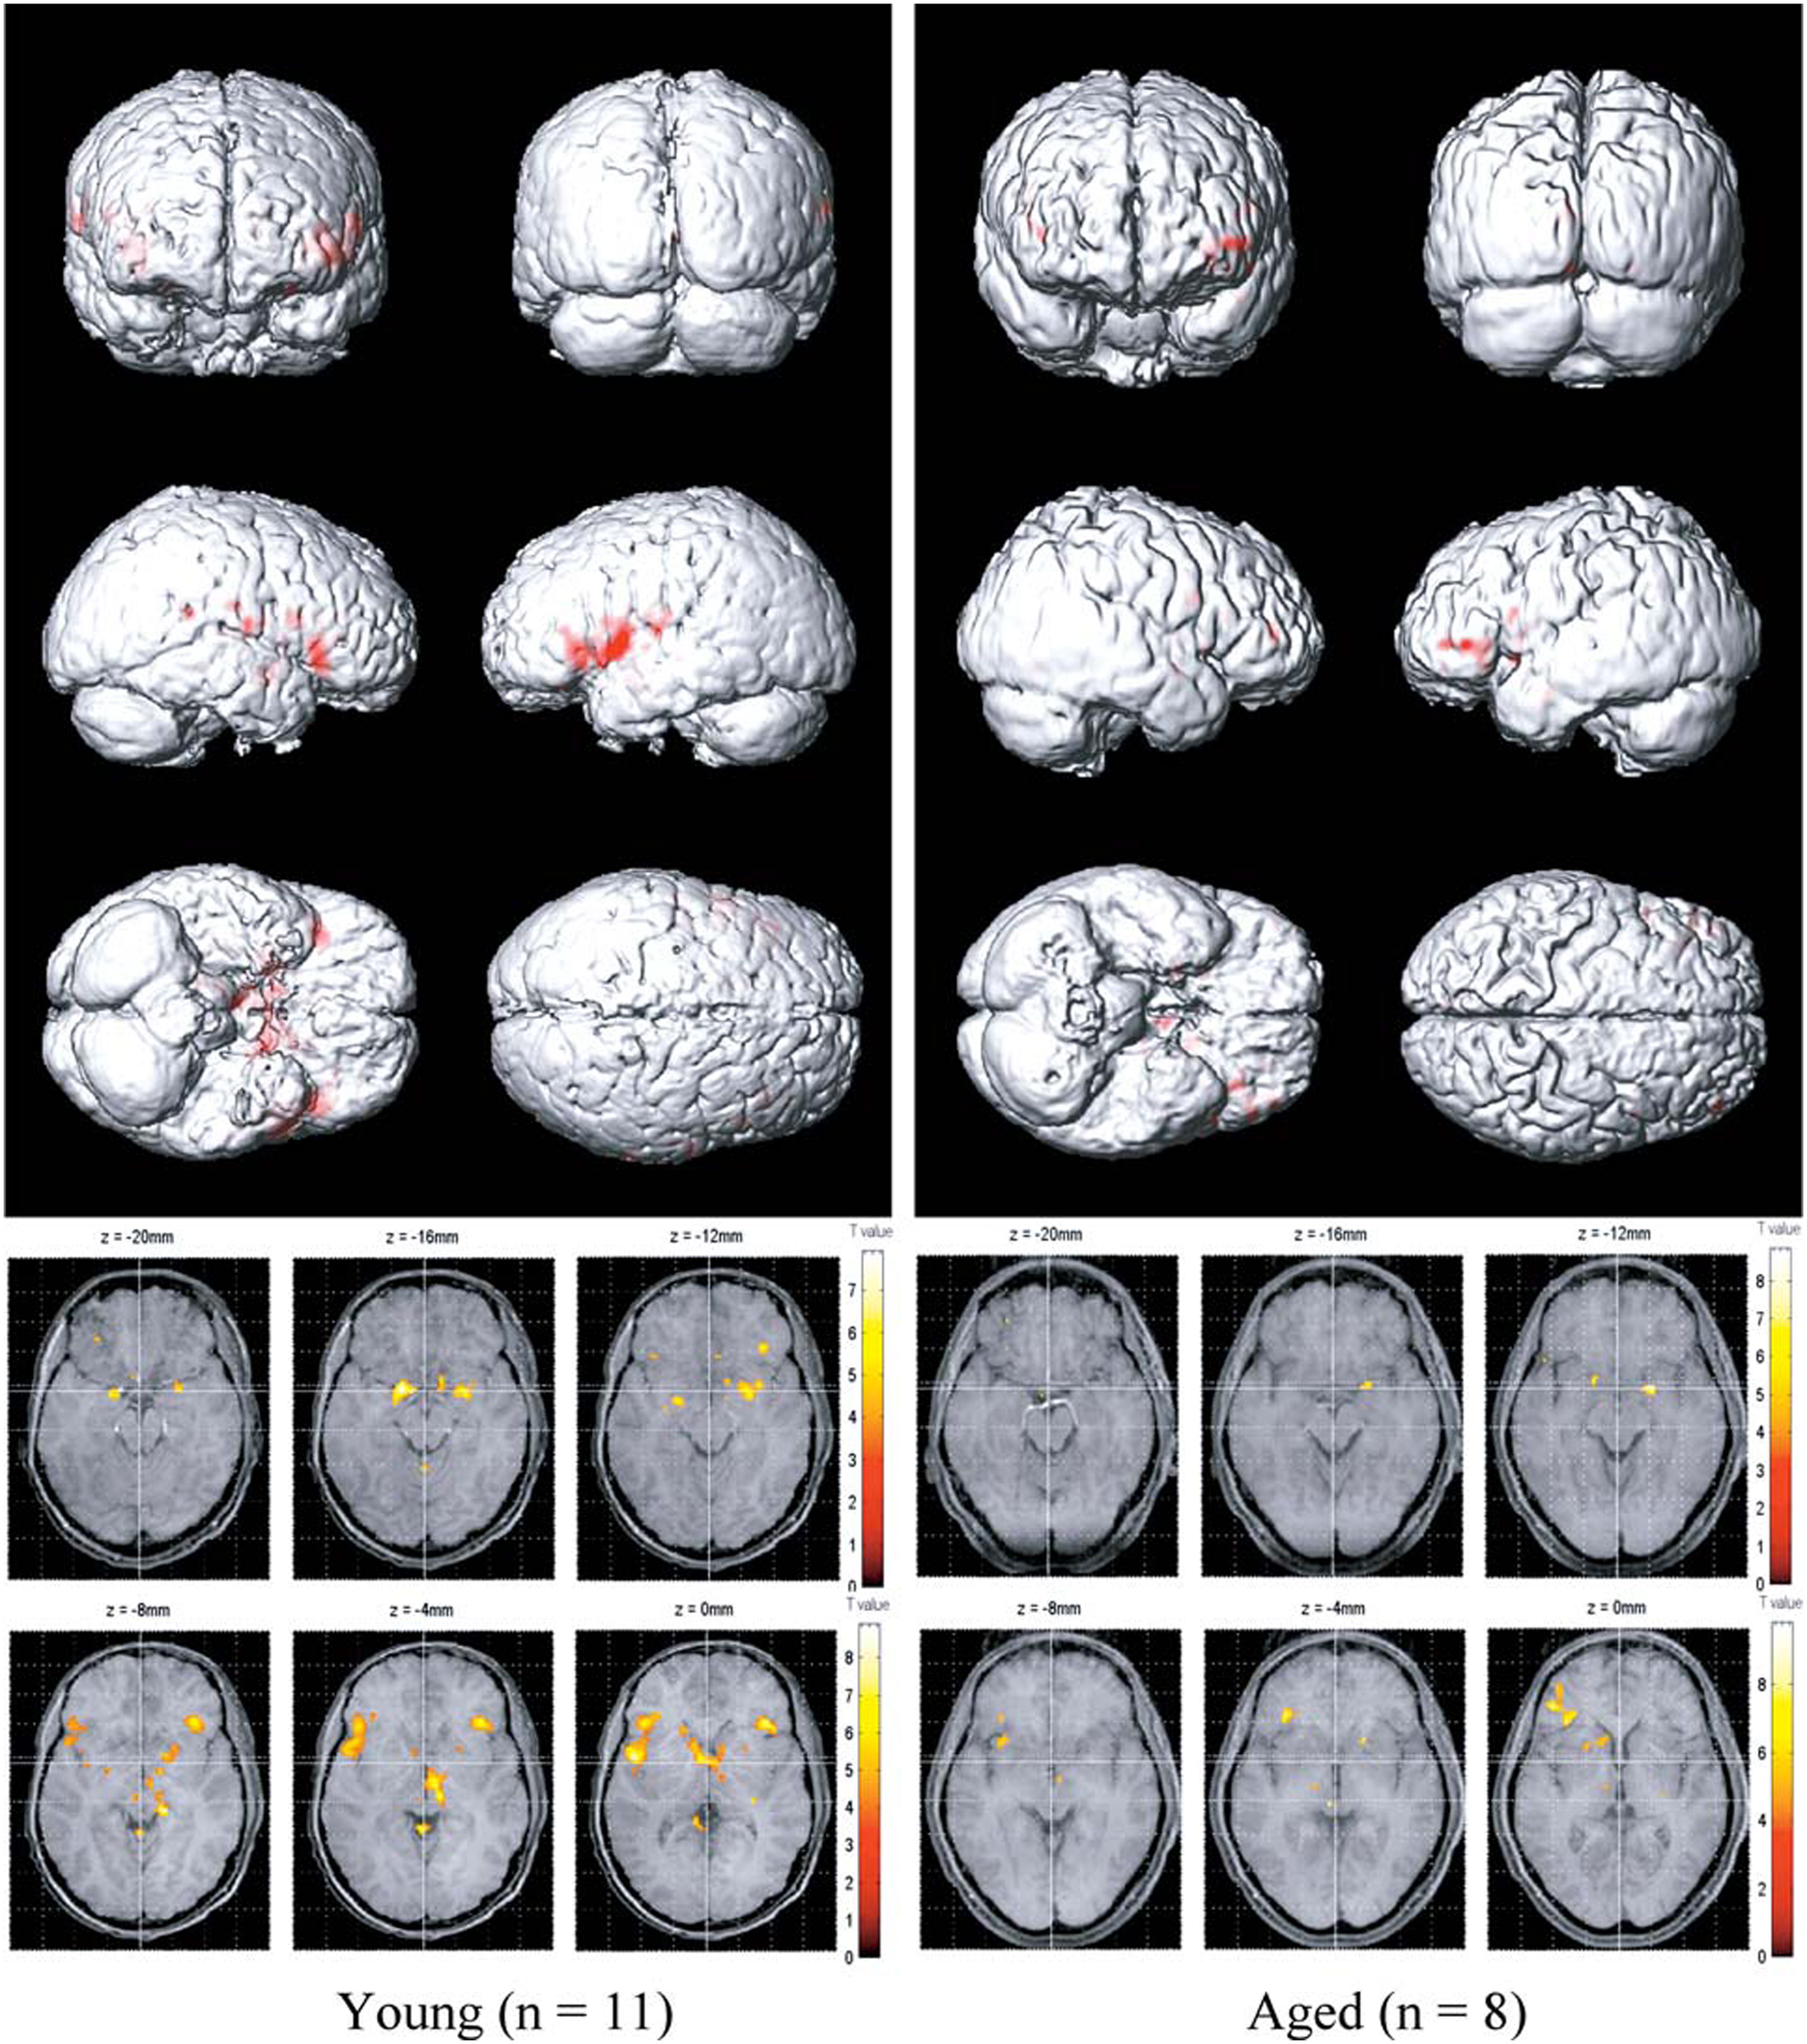

Functional imaging studies, such as those employing fMRI and positron emission tomography (PET), also demonstrate age-related changes in the processing of olfactory information, as reflected by decrements in odor-induced activation in central olfactory pathways. It should be noted, however, that such decrements need not be indicative of the locus of dysfunction. This is because the activity of a given central brain region often depends upon input from other brain regions that themselves may be compromised. Nevertheless, such imaging does represent the overall functioning of the system. Yousem et al., in a pioneering fMRI study, found that odors activated fewer voxels within the right inferior frontal and left and right superior frontal and perisylvian zones in old than in young persons (Yousem et al., 1999). Subsequently, Suzuki and his associates noted less fMRI odor-induced activation in 6 older persons than in 6 younger persons during an odor discrimination task in a region within the left orbital pole (Suzuki et al., 2001). Wang et al. (2005) found age-related decreases in activation in structures comprising the primary olfactory cortex, most notably in the right amygdala and piriform and periamygdaloid cortices (Figure 13). These investigators chose subjects whose UPSIT scores were within the normal age-adjusted range, although slightly lower scores were evident in the 11 young subjects (mean age = 23.9) than in the 8 older subjects (mean age = 66.4); respective UPSIT means = 37.3 and 34.1, p = 0.0004. More recently, Wong et al. (2010) found that a measure of nigrostriatal denervation in healthy elderly persons over the age 60 years, as determined by PET imaging of the brain dopamine transporter (DAT), was significantly correlated with UPSIT scores, suggesting that age-related declines in nigrostriatal function may account, in part, for age-related losses in smell ability.

Figure 13

Olfactory functional magnetic resonance imaging (fMRI) activation maps from 11 younger (left; mean age = 23.9 years) and 8 older (right; mean age = 66.4 years) persons to lavender and spearmint odors. Note greater activation in the younger subjects. From Wang et al. (2005), with permission. Copyright©2005, Gerontological Society of America.